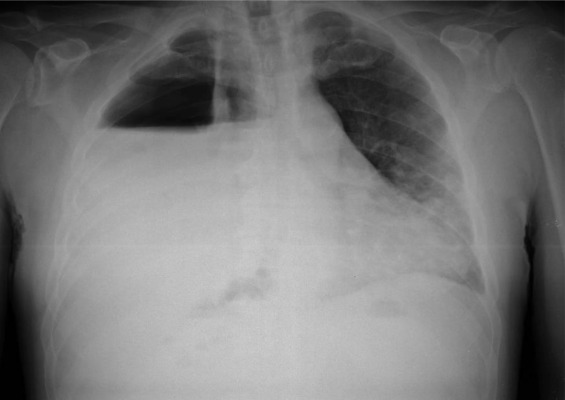

Examination finding in pleural effusion:

- Chest wall movement : Reduced in affected side

- trachea and mediastinum shift away from affected side

- With massive effusion (>1000ml)]

- Percussion note: Stony dull

- Breath sounds: Vesicular

- (Reduced or absent)

- Vocal resonance: Reduced or absent

Lateral decubitus x ray in pleural effusion:

- Demonstrates fluidity

- Suggest for thoracentesis if fluid layer > 1cm.